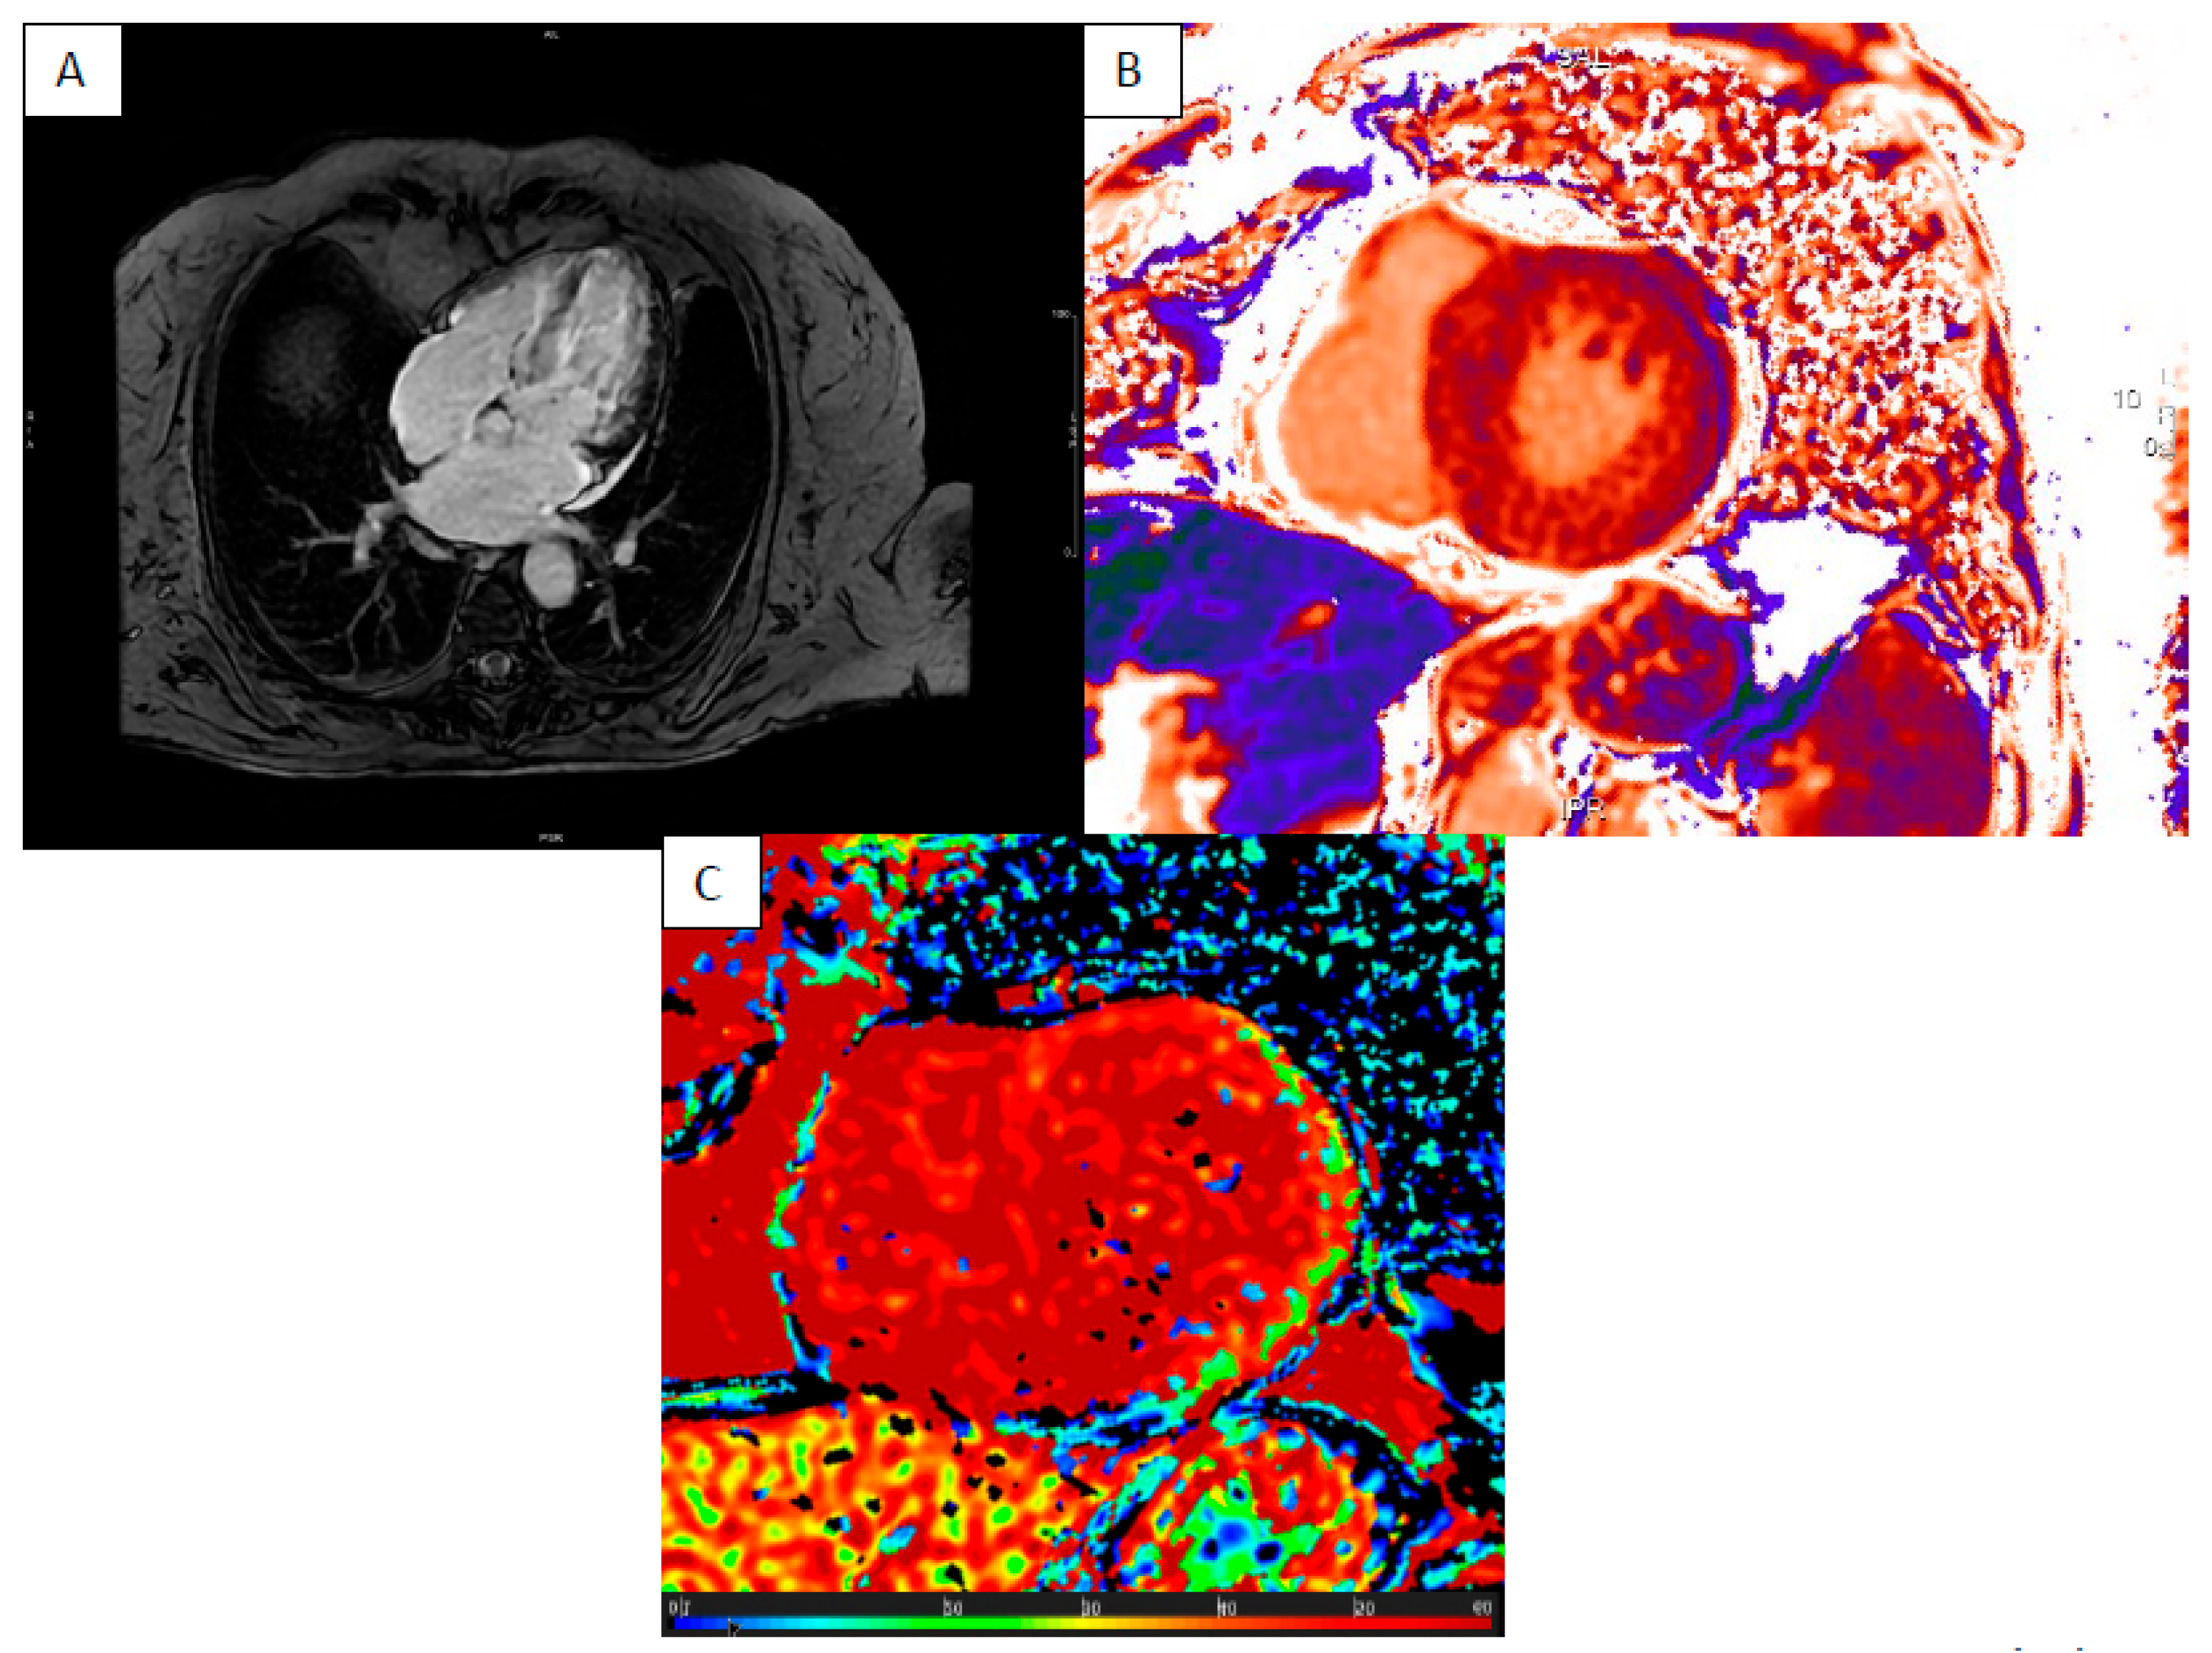

5. Anderson–Fabry Disease